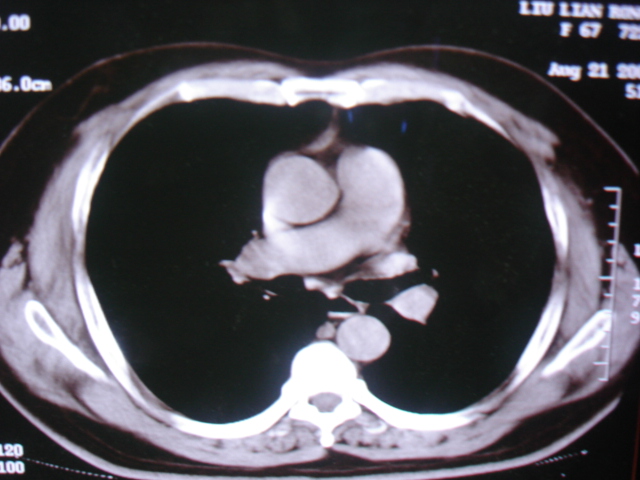

第一次ct2009.6.4

第二次ct2009.6.7 住院后ect未见异常,查痰(阴性)大量抗菌素抗炎一个月后病灶明显变小,7月5号出院后回家后口服抗菌素45天

第三次ct2009.8.21

病灶与胸膜成直边征,考虑炎症假瘤可能性大。

考虑左肺上叶炎症感染(炎性假瘤可能)。

考虑 左肺上叶炎症感染 [炎性假瘤可能性大]。

考虑左肺上叶炎症感染,以炎性假瘤可能性大。